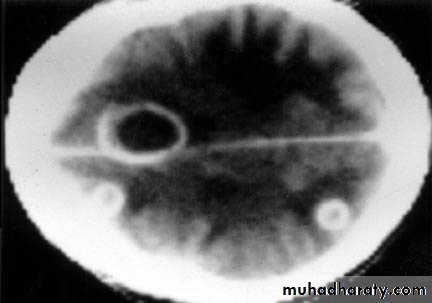

Stereotactic Aspiration of Brain Abscess

Multiple Abscesses

Deep Seated Abscess